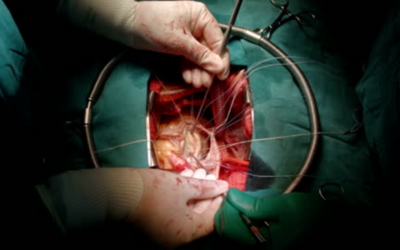

Open-Heart Surgery

In large defects that cause symptoms, open-heart surgery may be needed to close the defect. This is usually performed in infants or children who are not so responsive to catheter procedures.